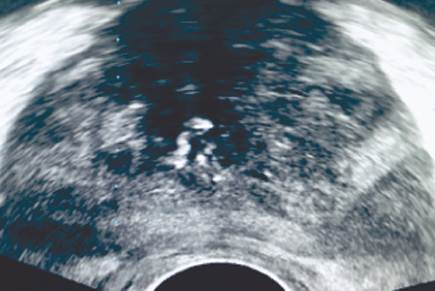

Figure 1 presents ultrasound imaging of the prostate gland with Doppler scanning of the vessels. This mode enables to map quite clearly the intraprostatic vessels, so damage should be avoided during the biopsy study. Figure 2 shows ultrasound imaging of the prostate gland, without the use of Doppler scanning of the vessels, which practically does not enable the determination of their distribution in the prostate, which increases the probability of their damage when obtaining a biopsy material.

Fig. 2. Ultrasound imaging of the prostate without Doppler control

Рис. 2. Ультразвуковая визуализация предстательной железы без доплеровского контроля